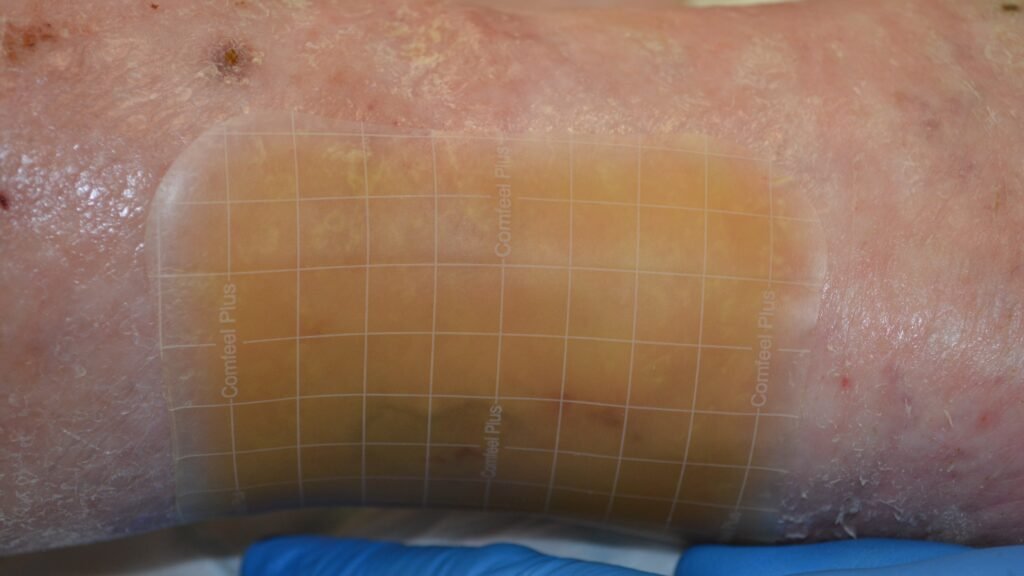

Comfeel Plus Contouriert

Comfeel Plus Flexibel

Comfeel Plus Flexibel, Sakrum

Comfeel Plus Transparent